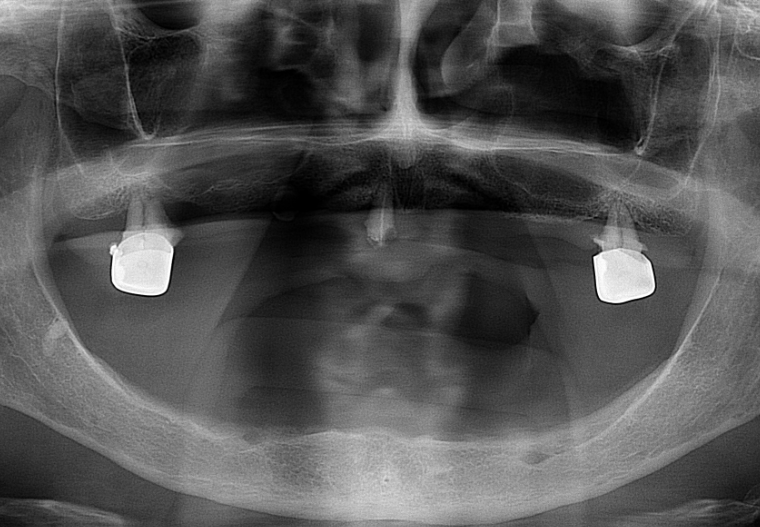

Az alapos szájüregi vizsgálatból és a röntgenfelvételből kiderült, hogy a felső állcsonton megmaradt fogak már nem tarthatók meg, így azok eltávolítása után alulra és felülre is teljes lemezes kivehető pótlást terveztünk páciensünk számára.

Fogpótlás teljes lemezes röngtenfelvétel